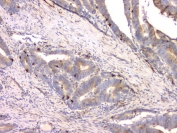

IHC staining of FFPE human colon cancer with Cystatin C antibody. HIER: boil tissue sections in pH8 EDTA for 20 min and allow to cool before testing.